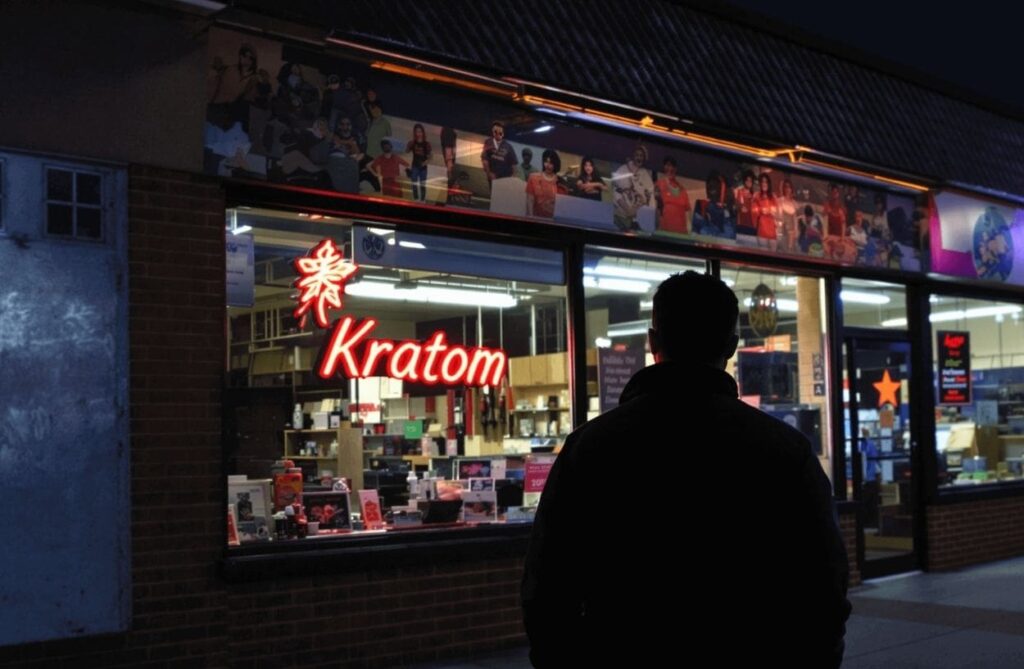

How to quit 7-OH and start feeling like yourself again

You might be here because you’ve been using kratom or a product with 7-OH, and lately… something doesn’t feel right. Maybe it started as a way to manage pain, boost…

You might be here because you’ve been using kratom or a product with 7-OH, and lately… something doesn’t feel right. Maybe it started as a way to manage pain, boost…